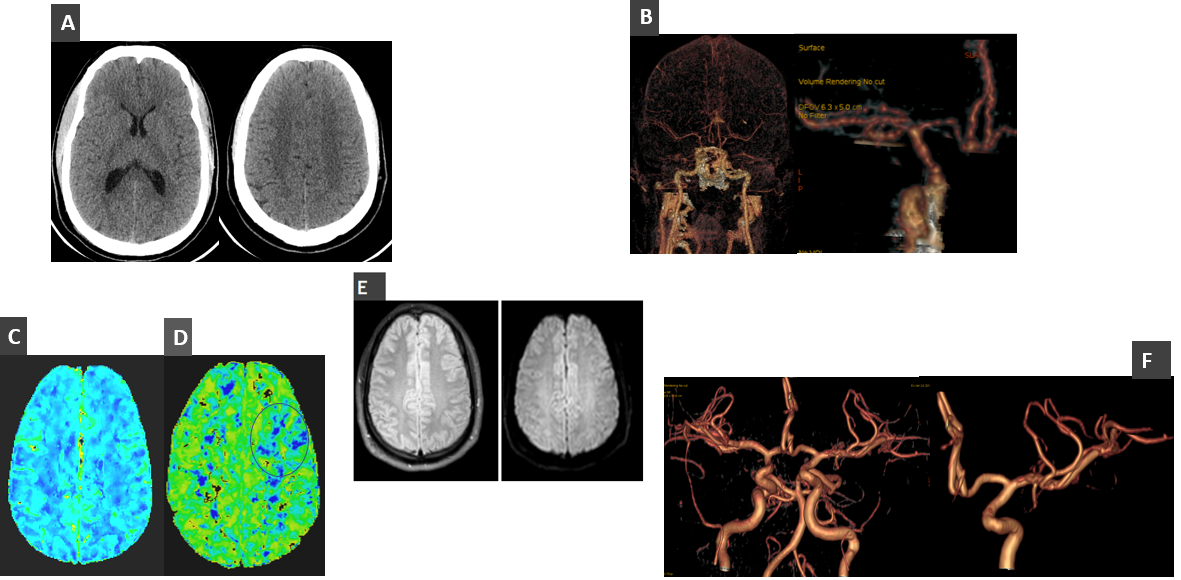

Mujer de 27 años • Antecedente de traumatismo craneoencefálico reciente. • Acude a urgencias por cefalea frontoparietal izquierda, afasia con parafasias, alexia y agrafia de tiempo de evolución incierto. • Se procede a activación de Código Ictus, por lo que se realiza TC cerebral basal, angioTC TSA e intracraneal, así como estudio perfusional. • Re realiza RM de control 5 días después.

A. TC cerebral basal sin alteraciones significativas.

B. Angio-TC (Volume rendering) que muestra una reducción global del calibre de las principales arterias del polígono de Willis con áreas de estenosis/dilatación (“collar de perlas”).

C. Mapa perfusional CVB sin alteraciones.

D. Mapa perfusional TTM con dudosa área de retraso frontal izquierdo.

E. RM cerebral sin alteraciones, se muestran secuencias FLAIR y DIFUSIÓN respectivamente.

F. Angio-RM realizada 5 días después, que muestra un calibre normal de las arterias intracraneales

SÍNDROME DE VASOCONSTRICCIÓN REVERSIBLE.

Epidemiológicamente es más habitual que afecte a mujeres adultas entre 20 y 50 años.    Se caracteriza por una clínica de cefalea en trueno con o sin otra focalidad neurológica    y una vasoconstricción arterial cerebral reversible en imagen.    Puede ser espontáneo o secundario a múltiples trigger (medicación vasoactiva, drogas, Postparto, disección carotídea, traumatismos, tumores…).    Normalmente presenta un curso benigno.